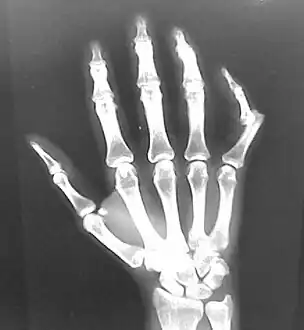

• Finger: Interphalangeal (IP) or metacarpophalangeal (MCP) joint dislocations[31]

• In the United States, men are most likely to sustain a finger dislocation with an incidence rate of 17.8 per 100,000 person-years.[32] Women have an incidence rate of 4.65 per 100,000 person-years.[32] The average age group that sustain a finger dislocation are between 15 and 19 years old.[32]